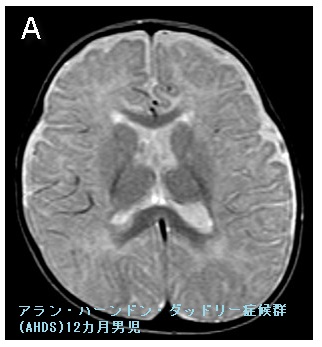

アラン・ハーンドン・ダッドリー症候群(AHDS:Allan-Herndon-Dudley syndrome)は、X連鎖性劣性遺伝のSLC16A2遺伝子変異によって、男性のみ発症。

脳細胞内に甲状腺ホルモンを取り込む甲状腺ホルモントランスポーター[Monocarboxylate transporter 8(MCT8)]に異常を来します。

胎内発育・生下時に問題はなく、新生児マススクリーニングをすり抜けます。

アラン・ハーンドン・ダッドリー症候群(AHDS)は、一般的な先天性甲状腺機能低下症(クレチン症)より

- 甲状腺機能低下症・成長障害が軽度(成長軟骨などのMCT10は無事のため)

- 乳児期より重度の精神発達遅滞・脳神経障害。てんかんの合併多い(脳はMCT8だけなので)

いわゆるフロッピー・インファント(下肢優位筋緊張低下)